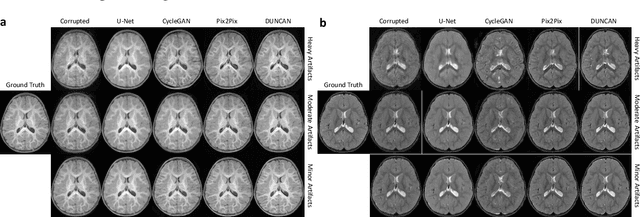

Abstract:Missing scans are inevitable in longitudinal studies due to either subject dropouts or failed scans. In this paper, we propose a deep learning framework to predict missing scans from acquired scans, catering to longitudinal infant studies. Prediction of infant brain MRI is challenging owing to the rapid contrast and structural changes particularly during the first year of life. We introduce a trustworthy metamorphic generative adversarial network (MGAN) for translating infant brain MRI from one time-point to another. MGAN has three key features: (i) Image translation leveraging spatial and frequency information for detail-preserving mapping; (ii) Quality-guided learning strategy that focuses attention on challenging regions. (iii) Multi-scale hybrid loss function that improves translation of tissue contrast and structural details. Experimental results indicate that MGAN outperforms existing GANs by accurately predicting both contrast and anatomical details.